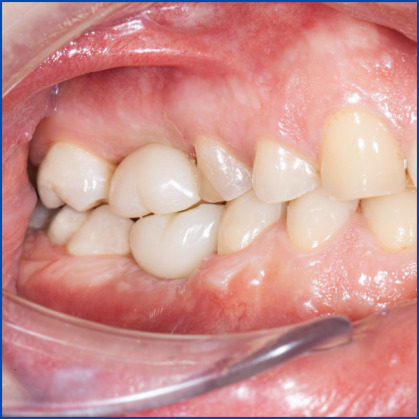

Kist nedeni ile çene kemiğinde defekt oluşmuş vakamıza sert ve yumuşak doku ogmentasyonu uyguladık